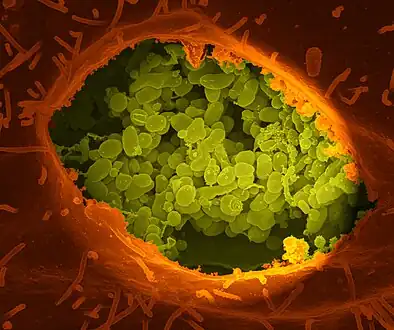

C. burnetii, the Q fever-causing agent A dry fracture of a Vero cell exposing the contents of a vacuole where Coxiella burnetii are busy growing

A dry fracture of a Vero cell exposing the contents of a vacuole where Coxiella burnetii are busy growing